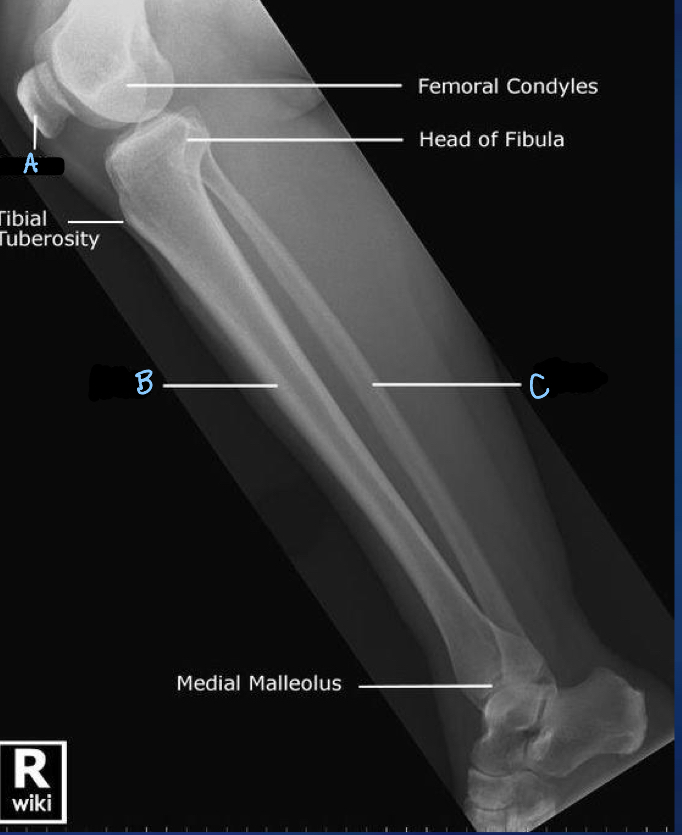

1

What is A?

lateral tibial condyle

2

What is B?

fibula

3

What is C?

medial tibial condyle

4

What is D?

tibia